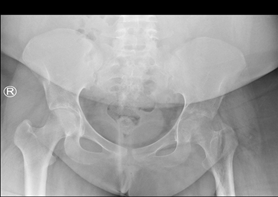

The X-ray test revealed focal cortical thickening involving the medial aspect of the femur’s proximal diaphysis, along with no definite fracture or bone lesion (Figure 1). The CT test revealed medial focal cortical thickening involving the proximal third of the femoral shaft (Figure 2).

Figure 1 X-ray pelvis with both hips anteroposterior view show focal cortical thickening involving the medial aspect of the proximal diaphysis of the femur, there is narrowing of the left hip joint. No definite fracture or bone lesion.